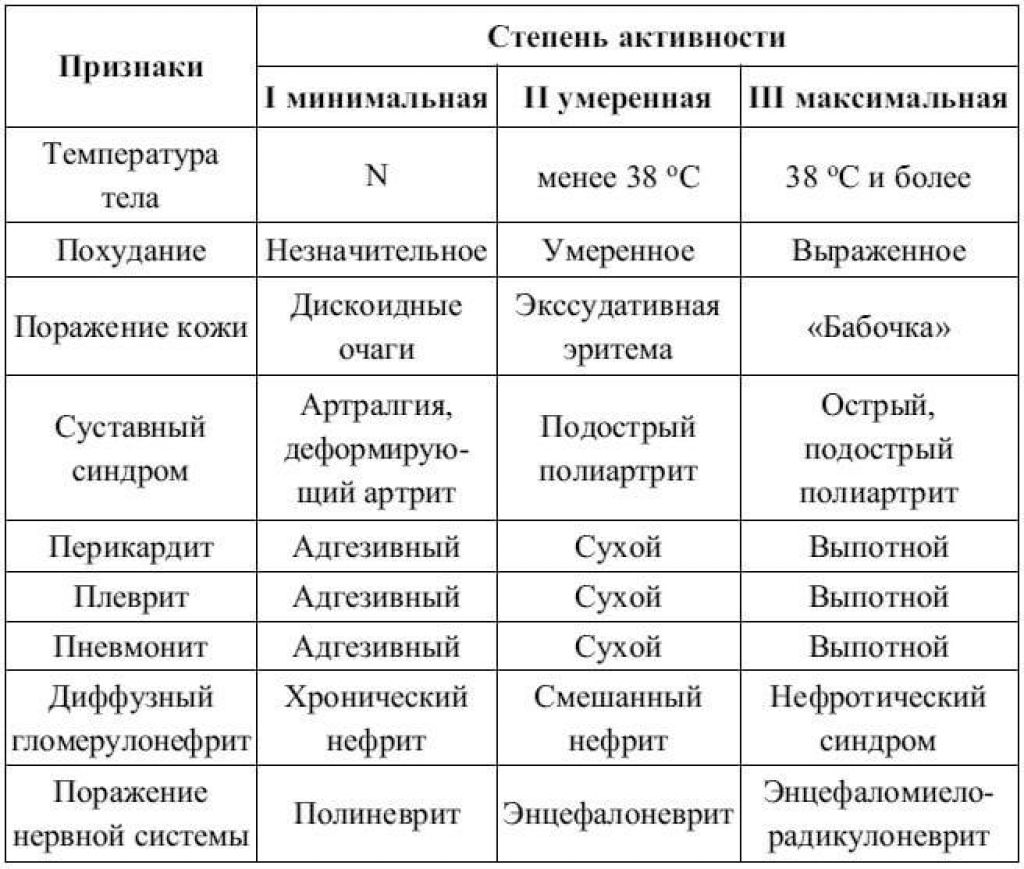

Признаки умеренно выраженной наружная

Признаки умеренно выраженной наружная 113 фото